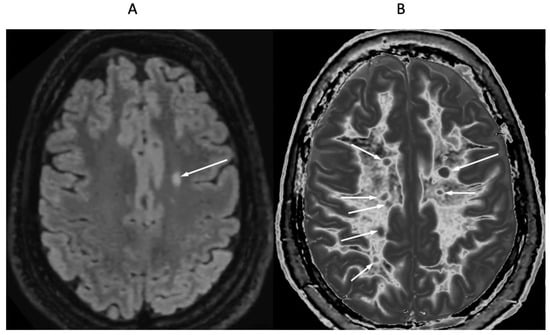

Figure 11 shows narrow mD dSIR images in a normal adult control (Figure 11A) and in a 77-year-old patient with MS (Figure 11B) during a relapse. In addition to the whiteout sign, there is a loss of contrast between gray and white matter in the thalamus of the patient (Figure 11B). Also, the heads of the caudate nuclei, as well as the insular and peripheral cortices, appear isointense with CSF on the dSIR image. These are grayout signs. No evidence of a whiteout sign or grayout signs was seen on the corresponding T2-FLAIR images.

Figure 11.

Skull-stripped images of a normal control (A) and 77-year-old patient with MS during a relapse (B). There is low signal in the normal white matter in (A) and a whiteout sign in (B). In addition, the gray matter in the thalamus and cortex has a uniform low signal and is nearly isointense with CSF. These are grayout signs. No evidence of a whiteout sign or grayout signs was seen on the positionally matched T2-FLAIR images.

5.2.2. Grayout Signs

Grayout signs can be manifest as a reduction or loss of contrast within a gray matter structure such as the thalamus, as well as reduction or loss of contrast between gray matter and white matter or between gray matter and CSF. On narrow mD dSIR sequences, a grayout sign can be caused by an increase in T1 in gray matter within the hD. Not infrequently, grayout signs are seen with higher grade whiteout signs, and, thus are features of an encephalopathy rather than a leucoencephalopathy (when only white matter is involved).